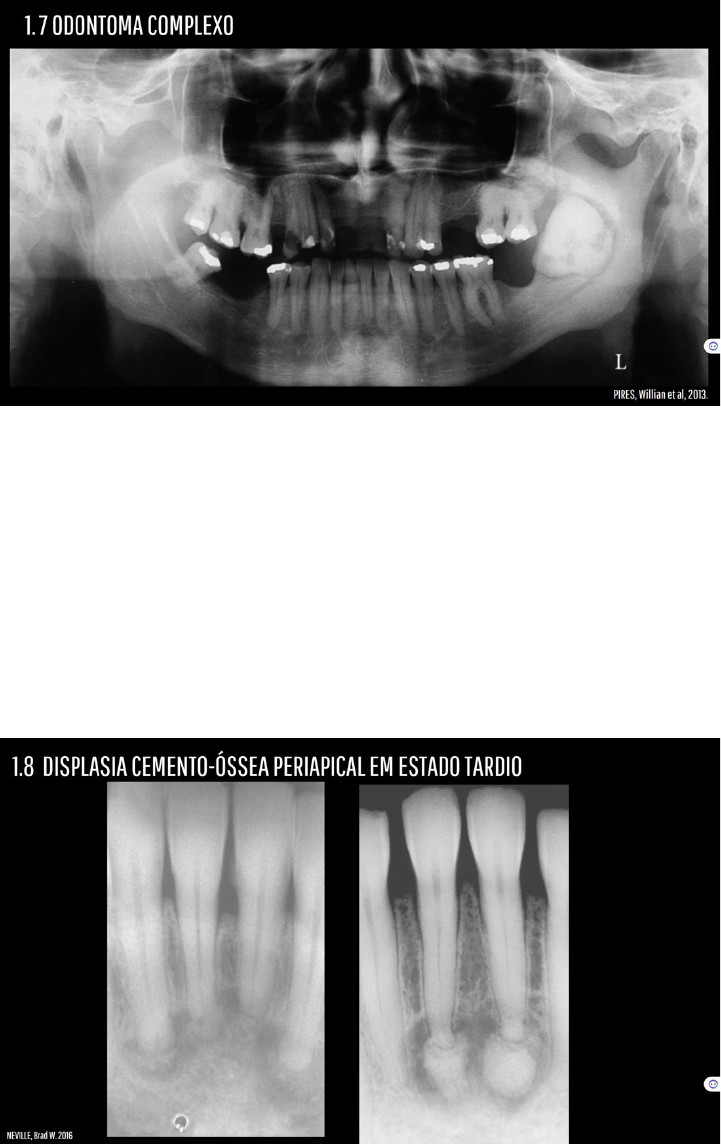

Grátis: ASPECTO RADIOGRAFICOS DAS LESÕES FIBRÓSSEAS E OSTOMIELITES - Material Claro e Objetivo em PDF para Estudo Rápido